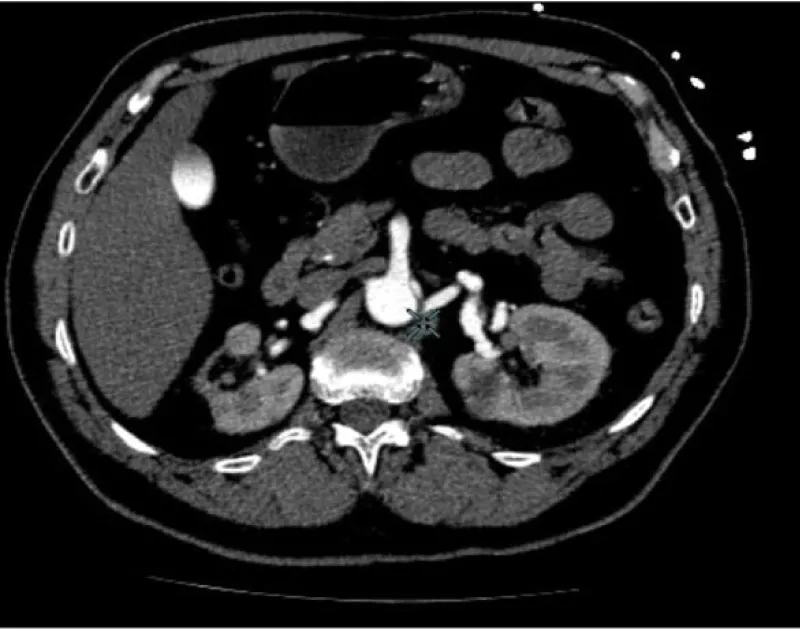

No acute ST-T abnormalities with biomarkers (troponin T and CK) repeatedly in the normal range. Normal blood count and coagulation studies. The patient is then admitted to the ICU. In the clinic of chest pain with negative electrical and enzymatic data, a CT scan is performed with intravenous contrast then unfold the existence of acute aortic syndrome Stanford type B (Figure 2). Transthoracic echocardiography was performed, showing preserved systolic function, without contractility alterations, without valvular disease but with slight left ventricular hypertrophy and slight pericardial effusion, with intimal flap distal to the left subclavian artery in the suprasternal plane.

Download Image

Figure 2: Lateral CT image where it can be an observed dissection of the aortic artery, with false lumen distal to left subclavian artery to the abdominal aorta without affecting the aortic arch (Stanford type B).